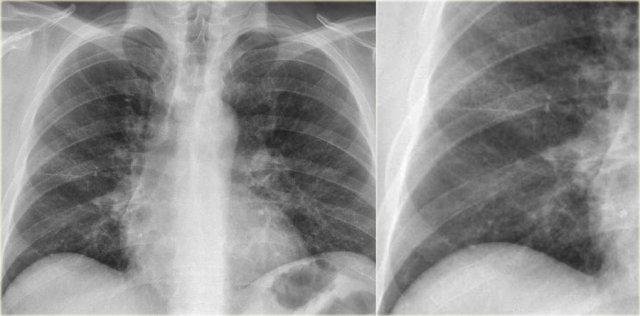

Xẹp thùy giữa phổi phải

Hãy quan sát kỹ các hình X-quang trước, sau đó tiếp tục đọc.

Các dấu hiệu là gì?

- Xóa mờ bờ tim phải (dấu hiệu bóng mờ)

- Đám mờ hình tam giác trên phim nghiêng do xẹp thùy giữa

Thông thường, xẹp thùy giữa phổi phải không gây nâng cao cơ hoành phải đáng kể.

Ngực lõm (pectus excavatum) có thể bắt chước hình ảnh xẹp thùy giữa trên phim thẳng, nhưng phim nghiêng sẽ giúp phân biệt được vấn đề này.